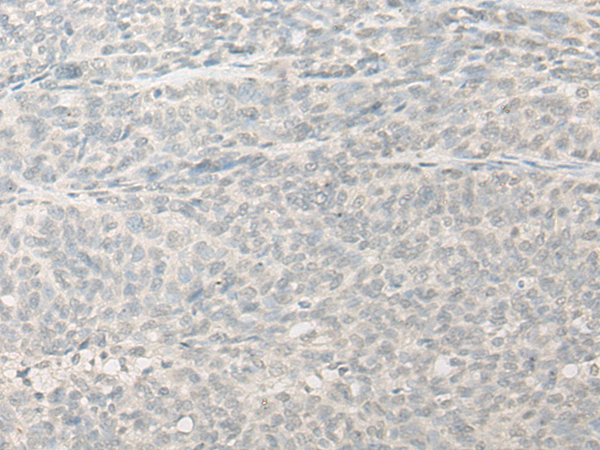

IHC positive control: |

Human ovarian cancer |

IHC Recommend dilution: |

25-100 |